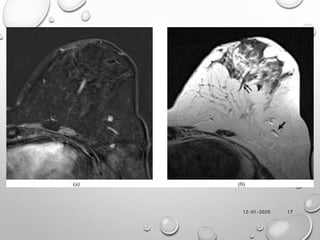

• INTRA-MAMMARY LYMPH NODES ARE USUALLY

LOCATED IN THE UPPER OUTER QUADRANT, THEY

MAY APPEAR ANYWHERE IN THE BREAST.

• NORMAL LYMPH NODES HAVE A WELL-DEFINED

MARGIN, CONTAIN A FATTY HILUM, ARE

ADJACENT TO A VESSEL AND HAVE A ROUND,

OVAL OR (MORE TYPICALLY) RENIFORM SHAPE.

• THEY ALSO SHOW HIGH SIGNAL INTENSITY ON T2

WEIGHTED IMAGES. CONVERSELY, ENHANCEMENT

CHARACTERISTICS ARE NOT HELPFUL BECAUSE

NORMAL LYMPH NODES MAY AVIDLY ENHANCE.

12-01-2020 17

• #18 Normal enhancing breast structures. (a) On the subtracted axial image of the left breast, four enhancing structures are seen: two are linear and two are nodular. (b) On the T2 weighted image, the two nodules have a location within fat and a hypersignal highly suggestive of lymph nodes, and the two linear structures are suggestive of vessels with one in hypersignal (arrow) and the other in hyposignal (double arrows) because of a difference in velocities